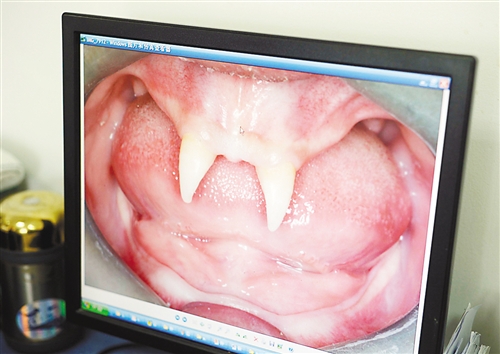

12月18日,16歲的張成(化名)從小到大,只有上顎部分有兩顆牙,看上去更像長著一對獠牙。 記者熊明攝

張成是貴州銅仁地區(qū)思南縣人,從生下來就似乎得了一種怪病,身上毛發(fā)稀少,面部發(fā)育也不好。更奇怪的是,別人家的孩子都長牙吃東西了,他卻一直長不出牙齒,最后只在上顎部分冒出兩顆比較突出且對稱的牙齒,看起來就像一對獠牙。

在母親陪同下,張成來到西南醫(yī)院口腔頜面外科就診。經(jīng)醫(yī)生檢查,張成被確診為無汗型外胚層發(fā)育不良。